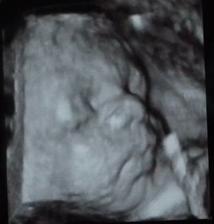

áno, aj mne sa veľmi páči, hneď ako som otehotnela som vedela, že to bude Martinko 🙂)) ale aj Tomáško je krásne meno 😉